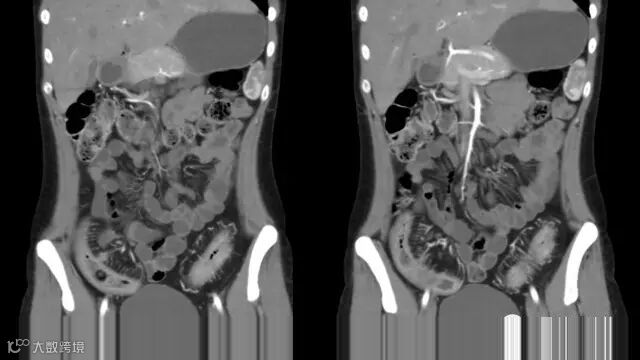

do you know comb sign?

The comb sign refers to the hypervascular appearance of the mesentery in active Crohn disease.

Very impressive image